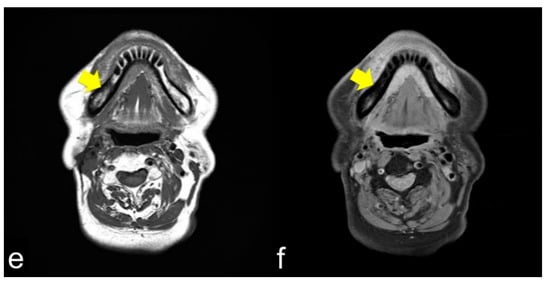

The same lesions captured by PET/CT and SPECT are shown in Figure 4a,b, respectively. PET/CT is useful for differentiating tumor recurrence. On the other hand, SPECT provides useful information regarding bone activity. PET/CT appeared to represent glucose metabolism, including the bone marrow, which was hyper-metabolized, and SPECT appeared to represent areas of increased bone metabolism; PET reflected inflammatory soft tissue and/or tumor recurrence and SPECT showed inflammatory and/or neoplastic bone tissue. PET/CT and SPECT are sensitive indicators of altered osteoblastic activity, but local disturbances in vascular perfusion, clearance rate, permeability, and chemical binding also affect imaging [13]. It is occasionally difficult to differentiate soft tissue uptake from bone uptake in patients with known cellulitis and possible underlying osteomyelitis. In terms of tumor recurrence, PET/CT and SPECT is useful but not definitive. Incisional biopsy is required for the final diagnosis.

Figure 4.

PET/CT (a) and single-photon emission computed tomography (SPECT) (b) images of the same lesion. PET/CT clearly shows soft tissue inflammation around the ORN area, while SPECT specifically shows bone inflammation. This comparison would help detect tumor recurrence.